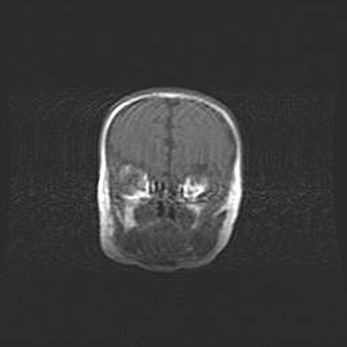

Наружная гидроцефалия с возможной атрофией височных областей.

Возраст: 28 дней

Вес: 3670 г

Пол: мужской

Окружность головы: 38 см

Срок гестации: 40 недель

Гидроцефалия головного мозга у новорожденных – это заболевание, которое характеризуется скоплением избыточного количества спинномозговой жидкости в желудочковой системе головного мозга в результате затруднения её перемещения от места выработки к месту поглощения в кровеносную систему или вследствие нарушения абсорбции. При открытой наружной форме гидроцефалии у новорожденных расширяются и переполняются субарахноидные пространства.

При нормотензивных  формах,  которые,  как  правило,  являются  следствием  перенесенных ишемических  повреждений  паренхимы  мозга,  возможно  сочетание микроцефалии  с нормотензивной гидроцефалией. В основе данных изменений лежит атрофия больших полушарий с преимущественной  локализацией  в  лобно-височных  областях.